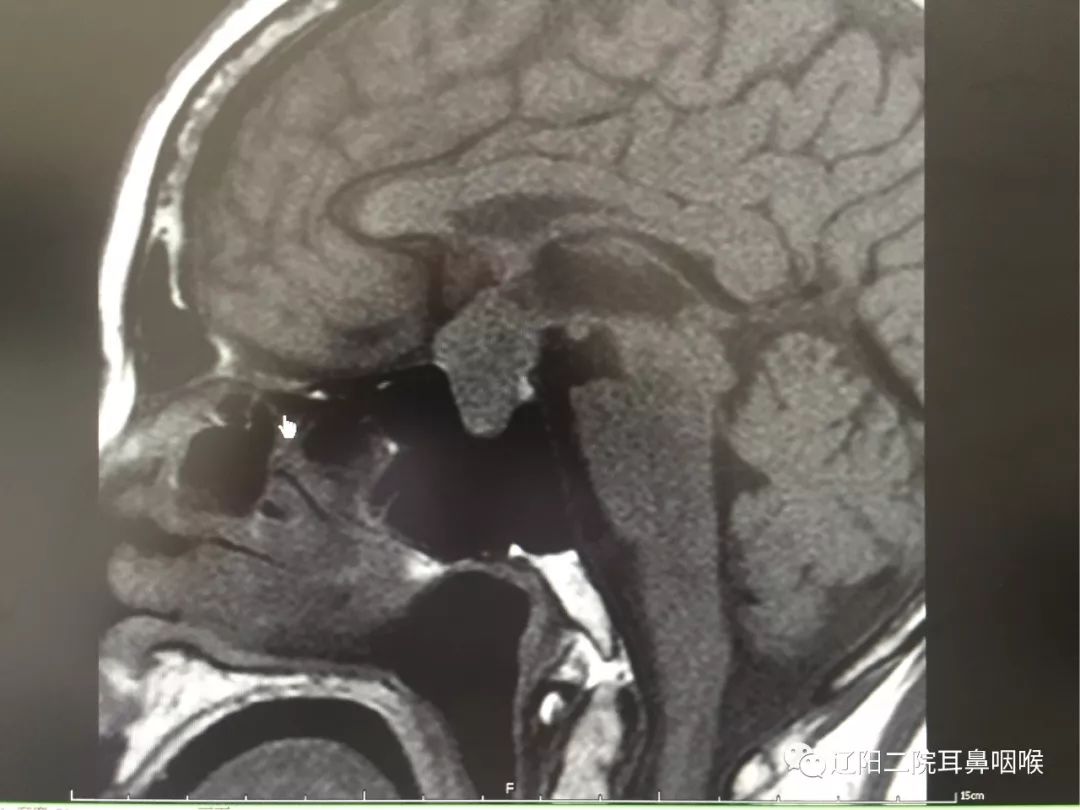

辽阳二院成功实施我市首例鼻内镜下经鼻腔蝶窦入路垂体瘤切除术

病例分享 经鼻蝶内镜分期切除巨大垂体腺瘤一例 神经内镜系列十九 浙二神外周刊 第277期 肿瘤